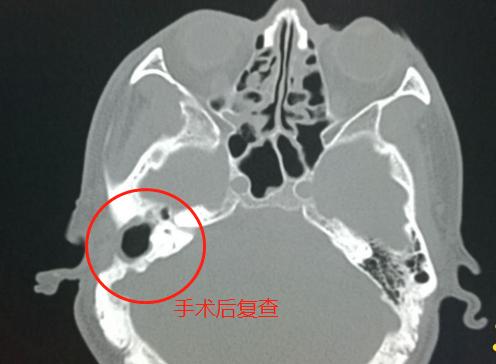

4.胆脂瘤形成,手术后图片——

右侧乳突手术后,局部骨质缺损